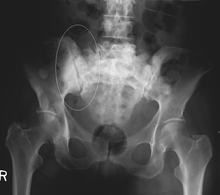

Sclerotic breast cancer metastases in the pelvis.

Example of a bone metastasis, showing location and appearance